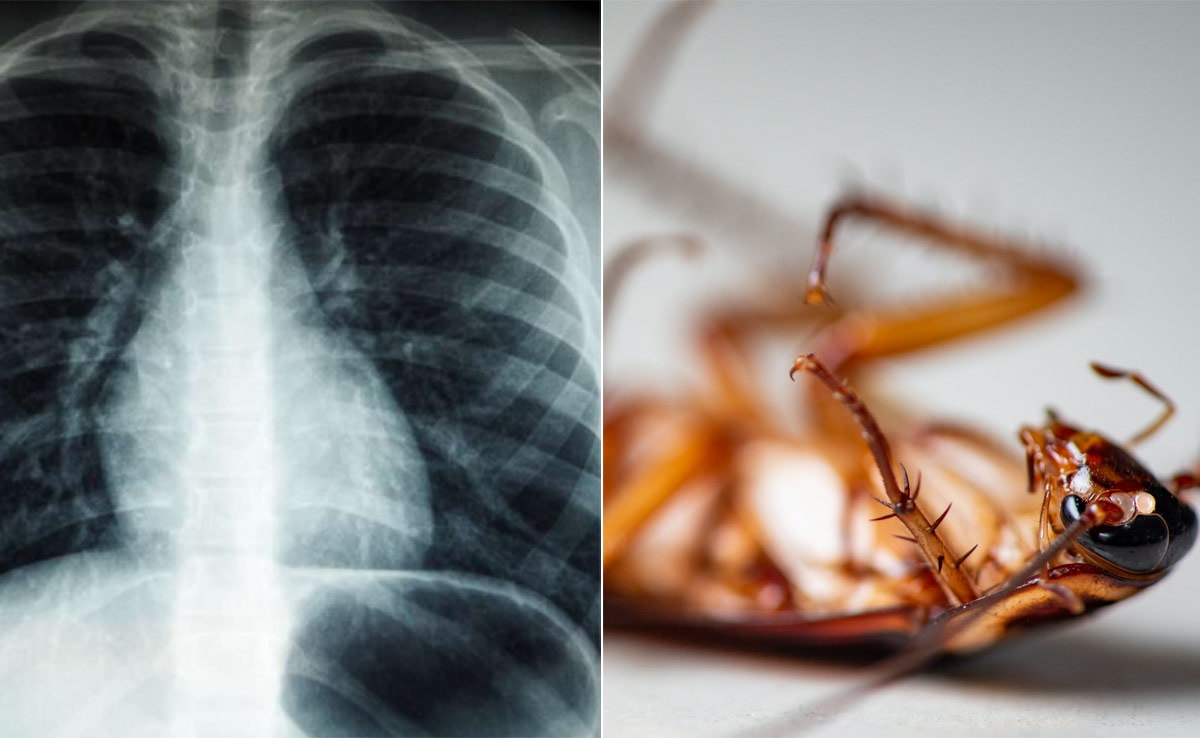

Doctors Remove 4 Cm Long Cockroach From Man Lungs: इंटरनेट पर अक्सर कुछ ऐसे मामले देखने और सुनने को मिल जाते हैं, जिन पर यकीन कर पाना मुश्किल हो जाता है. हाल ही में एक ऐसा ही चौंका देने वाला मामला केरल के कोच्चि से सामने आ रहा है, जिसके बारे में जानकर आप भी हैरान रह जाएंगे. दरअसल, कोच्चि में एक शख्स को सांस लेने में दिक्कत हो रही थी. जब ये समस्या लेकर शख्स डॉक्टर के पास पहुंचा और जांच हुई तो डॉक्टर भी हक्के-बक्के रह गए. दरअसल, डॉक्टर ने इलाज के दौरान शख्स के फेफड़े से 4 सेमी लंबा कॉकरोच निकाला है. सोशल मीडिया पर वायरल हो रहे इस मामाले को जानने के बाद पब्लिक भी शॉक्ड रह गई.

मीडिया रिपोर्ट के मुताबिक, डॉक्टरों की एक टीम के उस वक्त होश उड़ गए, जब उन्होंने सांस लेने में तकलीफ की शिकायत पर अस्पताल पहुंचे एक मरीज की जांच की. बताया जा रहा है कि, 55 वर्षीय मरीज का कोच्चि के एक अस्पताल में इलाज चल रहा था. इस बीच जब डॉक्टरों ने मरीज के फेफड़ों की जांच की, तो अंदर का नजारा हैरान कर देने वाला था. बताया जा रहा है कि, फेफड़े में चार सेमी लंबा एक कॉकरोच फंसा हुआ था, जिसके कारण शख्स को सांस लेने में दिक्कत हो रही थी. करीब 8 घंटे चले ऑपरेशन के बाद डॉक्टर कॉकरोच को निकालने में कामयाब रहे, फिलहाल मरीज अब बिल्कुल ठीक है और उसे अस्पताल से छुट्टी भी दे दी गई है.

रिपोर्ट के मुताबिक, कॉकरोच टुकड़ों में बिखर रहा था, जिसके कारण दिन-प्रतिदिन मरीज की श्वसन संबंधी स्थिति और खराब हो रही थी. कहा जा रहा है कि, मरीज के पिछले चिकित्सा उपचार के समय एक श्वास नली डाली गई थी. अनुमान लगाया जा रहा है कि, कॉकरोच उसी सांस नली से होता हुआ फेफड़े में प्रवेश कर गया होगा.